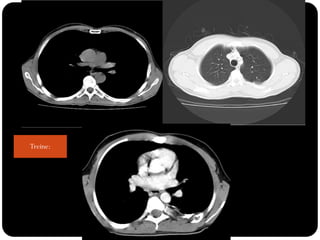

Treine...

Treine: